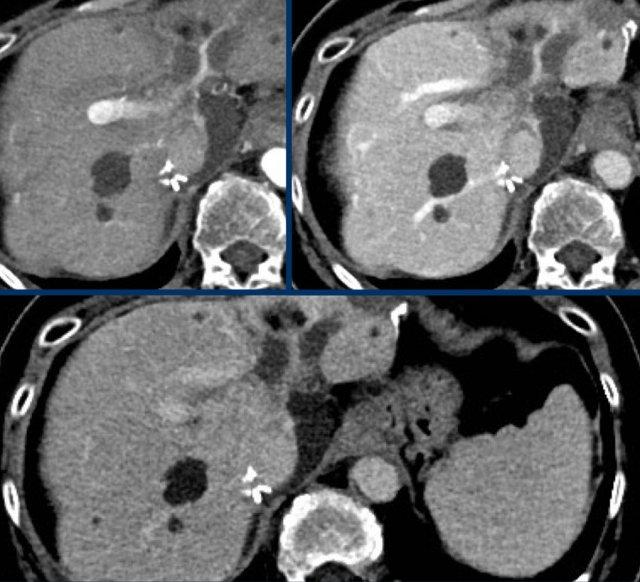

Các hình ảnh cho thấy các tổn thương không ngấm thuốc ở cả thì động mạch muộn, thì tĩnh mạch cửa và thì muộn.

Các hình ảnh CT cho thấy một tổn thương có kiểu ngấm thuốc theo huyết pool, đặc trưng cho u máu.

Tiếp tục xem hình ảnh MRI của bệnh nhân này.

Hình ảnh MRI của cùng bệnh nhân.

Kiểu ngấm thuốc của tổn thương này theo kiểu ngấm thuốc của huyết pool.